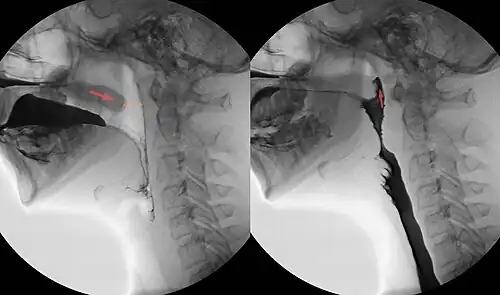

Der velopharyngeale Verschluss (VP-Verschluss; auch velopharyngealer Abschluss - VPA - oder nasopharyngealer Verschluss) ist der kurzzeitige physiologische Verschluss des Nasenrachens (lat. Nasopharynx) durch das Gaumensegel (lat. Velum palatinum; weicher Gaumen - lat. Palatum molle). Durch den velopharyngealen Verschluss wird der Nasopharynx gegenüber dem Oropharynx abgedichtet, während des Sprechens schließen die velopharyngealen Muskeln den Oro- und Nasopharynx - velopharyngealer Sphinkter. Er ist für das Schlucken oder die Aussprache bestimmter Verschlusslaute wichtig. Der velopharyngeale Verschluss trennt bei der Bildung nichtnasaler Laute den Oropharynx vom Nasopharynx.

Beim Schluckakt, in der pharyngealen Transportphase, verhindert der velopharyngeale Verschluss des Gaumensegels gegen die Rachenhinterwand den Übertritt des Nahrungsbreis in die oberen Luftwege. Während des velopharyngealen Verschlusses bildet sich durch die Kontraktion der Rachenhinterwand an dieser ein querverlaufender Wulst, der Passavantsche Wulst, der sich dem Gaumensegel entgegenstreckt und den Verschluss verbessert.

Das Gaumensegel wird durch den Musculus levator veli palatini (Hebemuskel des Gaumensegels) und den Musculus tensor veli palatini (Gaumensegelspanner) an die Rachenhinterwand und Seitenwände gepresst. Die Muskulatur der Rachenwände besteht aus dem Musculus constrictor pharyngis superior (oberer Schlundschnürer) und dem Musculus palatopharyngeus (Gaumenrachenmuskel).